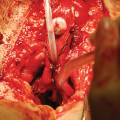

Bulbar Neourethra

Urethroplasty starts with the reconstruction of the bulbar part. One of the main advantages of this technique is the simultaneous removal of the vaginal mucosa and use of periurethral mucosa in creation of the bulbar urethra. Periurethral tissue proved to be better supportive material compared to the previously used vaginal flap, in terms of postoperative complications [2]. The bulbar urethra suffers the highest urinary stream pressure and therefore represents a high-risk point for postoperative fistula formation. The joining of the clitoral bulbs over the neourethra and the additional covering with vascularized surrounding tissue is considered a key for successful fistula prevention at the place of anastomosis with native female urethral orifice.

Further urethral lengthening is performed using a buccal mucosa or skin graft and vascularized genital skin flaps [20, 21]. Buccal mucosa graft has become the gold standard material in urethral reconstruction, especially due to its’ histological attributes. Graft harvesting is a safe procedure without morbidity of the donor site [15, 22]. The graft is prepared and sutured to cover the defect left after the division of the short urethral plate (Fig. 67.1b). Split-thickness skin graft can be used as an alternative, harvested from labia minora or other genital area. Quilting of the graft to the corporeal bodies is very important for better survival. Urethral reconstruction is completed either by using a longitudinal dorsal clitoral skin flap button-holed ventrally, or a flap harvested from the inner surface of the labia minora. Labial flap combined with buccal mucosa graft is reported as the best option, resulting in a complication rate lower than 7% [20]. Either skin or labial flap is joined with buccal mucosa graft over a 10–12 Fr catheter to form penile neourethra (Fig. 67.1c). In both cases, all suture lines are covered with well vascularized tissue to prevent fistula formation.